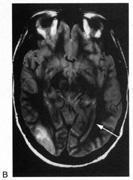

HEMIACHROMATOPSIA.

Achromatopsia in the contralateral hemifield alone can follow unilateral right or left occipital lesions (Fig. 18). Patients are typically asymptomatic until the defect is demonstrated on examination.234,235 Hemiachromatopsia is usually associated with a superior quadrantanopia;234,235,241 therefore, the color defect is only demonstrable in the remaining inferior quadrant. The preserved color vision in the ipsilateral hemifield allows normal or near-normal performance on centrally viewed tests of color vision such as pseudoisochromatic plates. The incidence of hemiachromatopsia is probably underestimated, given its asymptomatic nature and the failure of routine clinical color tests to detect its presence.

Fig. 18. Magnetic resonance imaging scan of patient with stroke causing a right hemiachromatopsia as well as partial superior quadrantanopia.